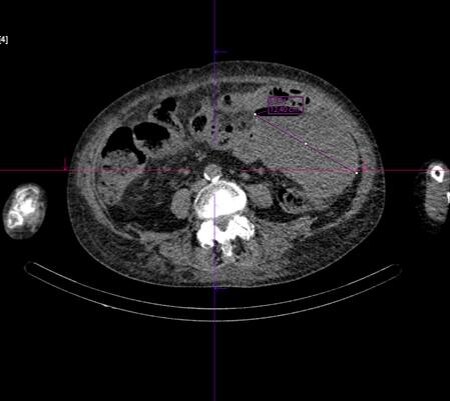

«Первое, что бросилось в глаза — это жидкостное образование с пузырьками и газами слева в брюшной полости, что указывало на наличие большой гнойной полости — абсцесса. Источником данного состояния стала перфорация опухоли сигмовидной кишки», - заключила врач-рентгенолог Татьяна Семенова.

По ее словам, при этом отдаленных метастазов данной опухоли в другие органы и ткани не обнаружено. Это говорит о том, что тяжесть состояния пациентки обусловлена именно массивным воспалительным процессом.